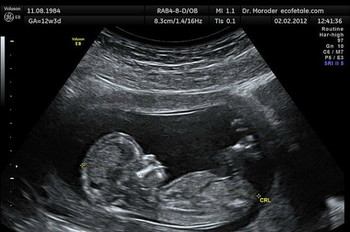

The baby’s mother had opted for an abortion at a hospital in Italy after prenatal scans suggested that her baby was disabled. However, the infant survived the procedure and was left by doctors to die. He was discovered alive the following day – some 20 hours after the operation – by Father Antonio Martello, the hospital chaplain, who had gone to pray beside his body. Sadly, the 22-week infant died one day later in the intensive care unit.